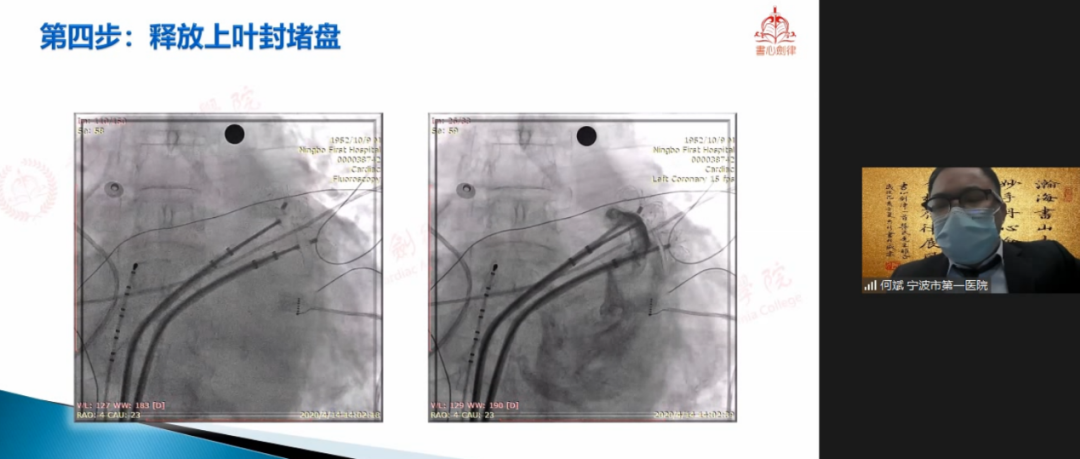

宁波市第一医院何斌教授在会议中与专家们共享LAmbre™双伞封堵大心耳经验。该病例为81岁男性,被诊断为持续性心房颤动,CHA2DS2-VASc评分6分、HAS-BLED评分4分,既往有左心耳血栓、卒中病史。抗凝治疗6月后,TEE下未见心耳血栓。术中DSA造影提示患者为双早分叶心耳,上叶梳状肌发达,下叶较为光滑,心耳口部直径45mm。已有临床实例表明,LAmbre™行双伞封堵具有可行性,结合患者情况、家属意愿及心耳形态等多种因素,何斌教授最终拟定为患者行双伞封堵策略。何斌教授首先行两次房间隔穿刺并再次造影确认心耳形态及大小,测量得上叶锚定区21.6mm,下叶锚定区19.4mm,随后选用LAmbre™2228封堵器先行封堵下叶,牵拉测试稳定后,选择LAmbre™2430封堵器封堵心耳上叶。最终,双伞牵拉测试稳定,TEE多角度评估双伞形态良好,紧密贴合,无明显残余分流,一年后随访结果显示,封堵效果良好,无卒中事件发生。